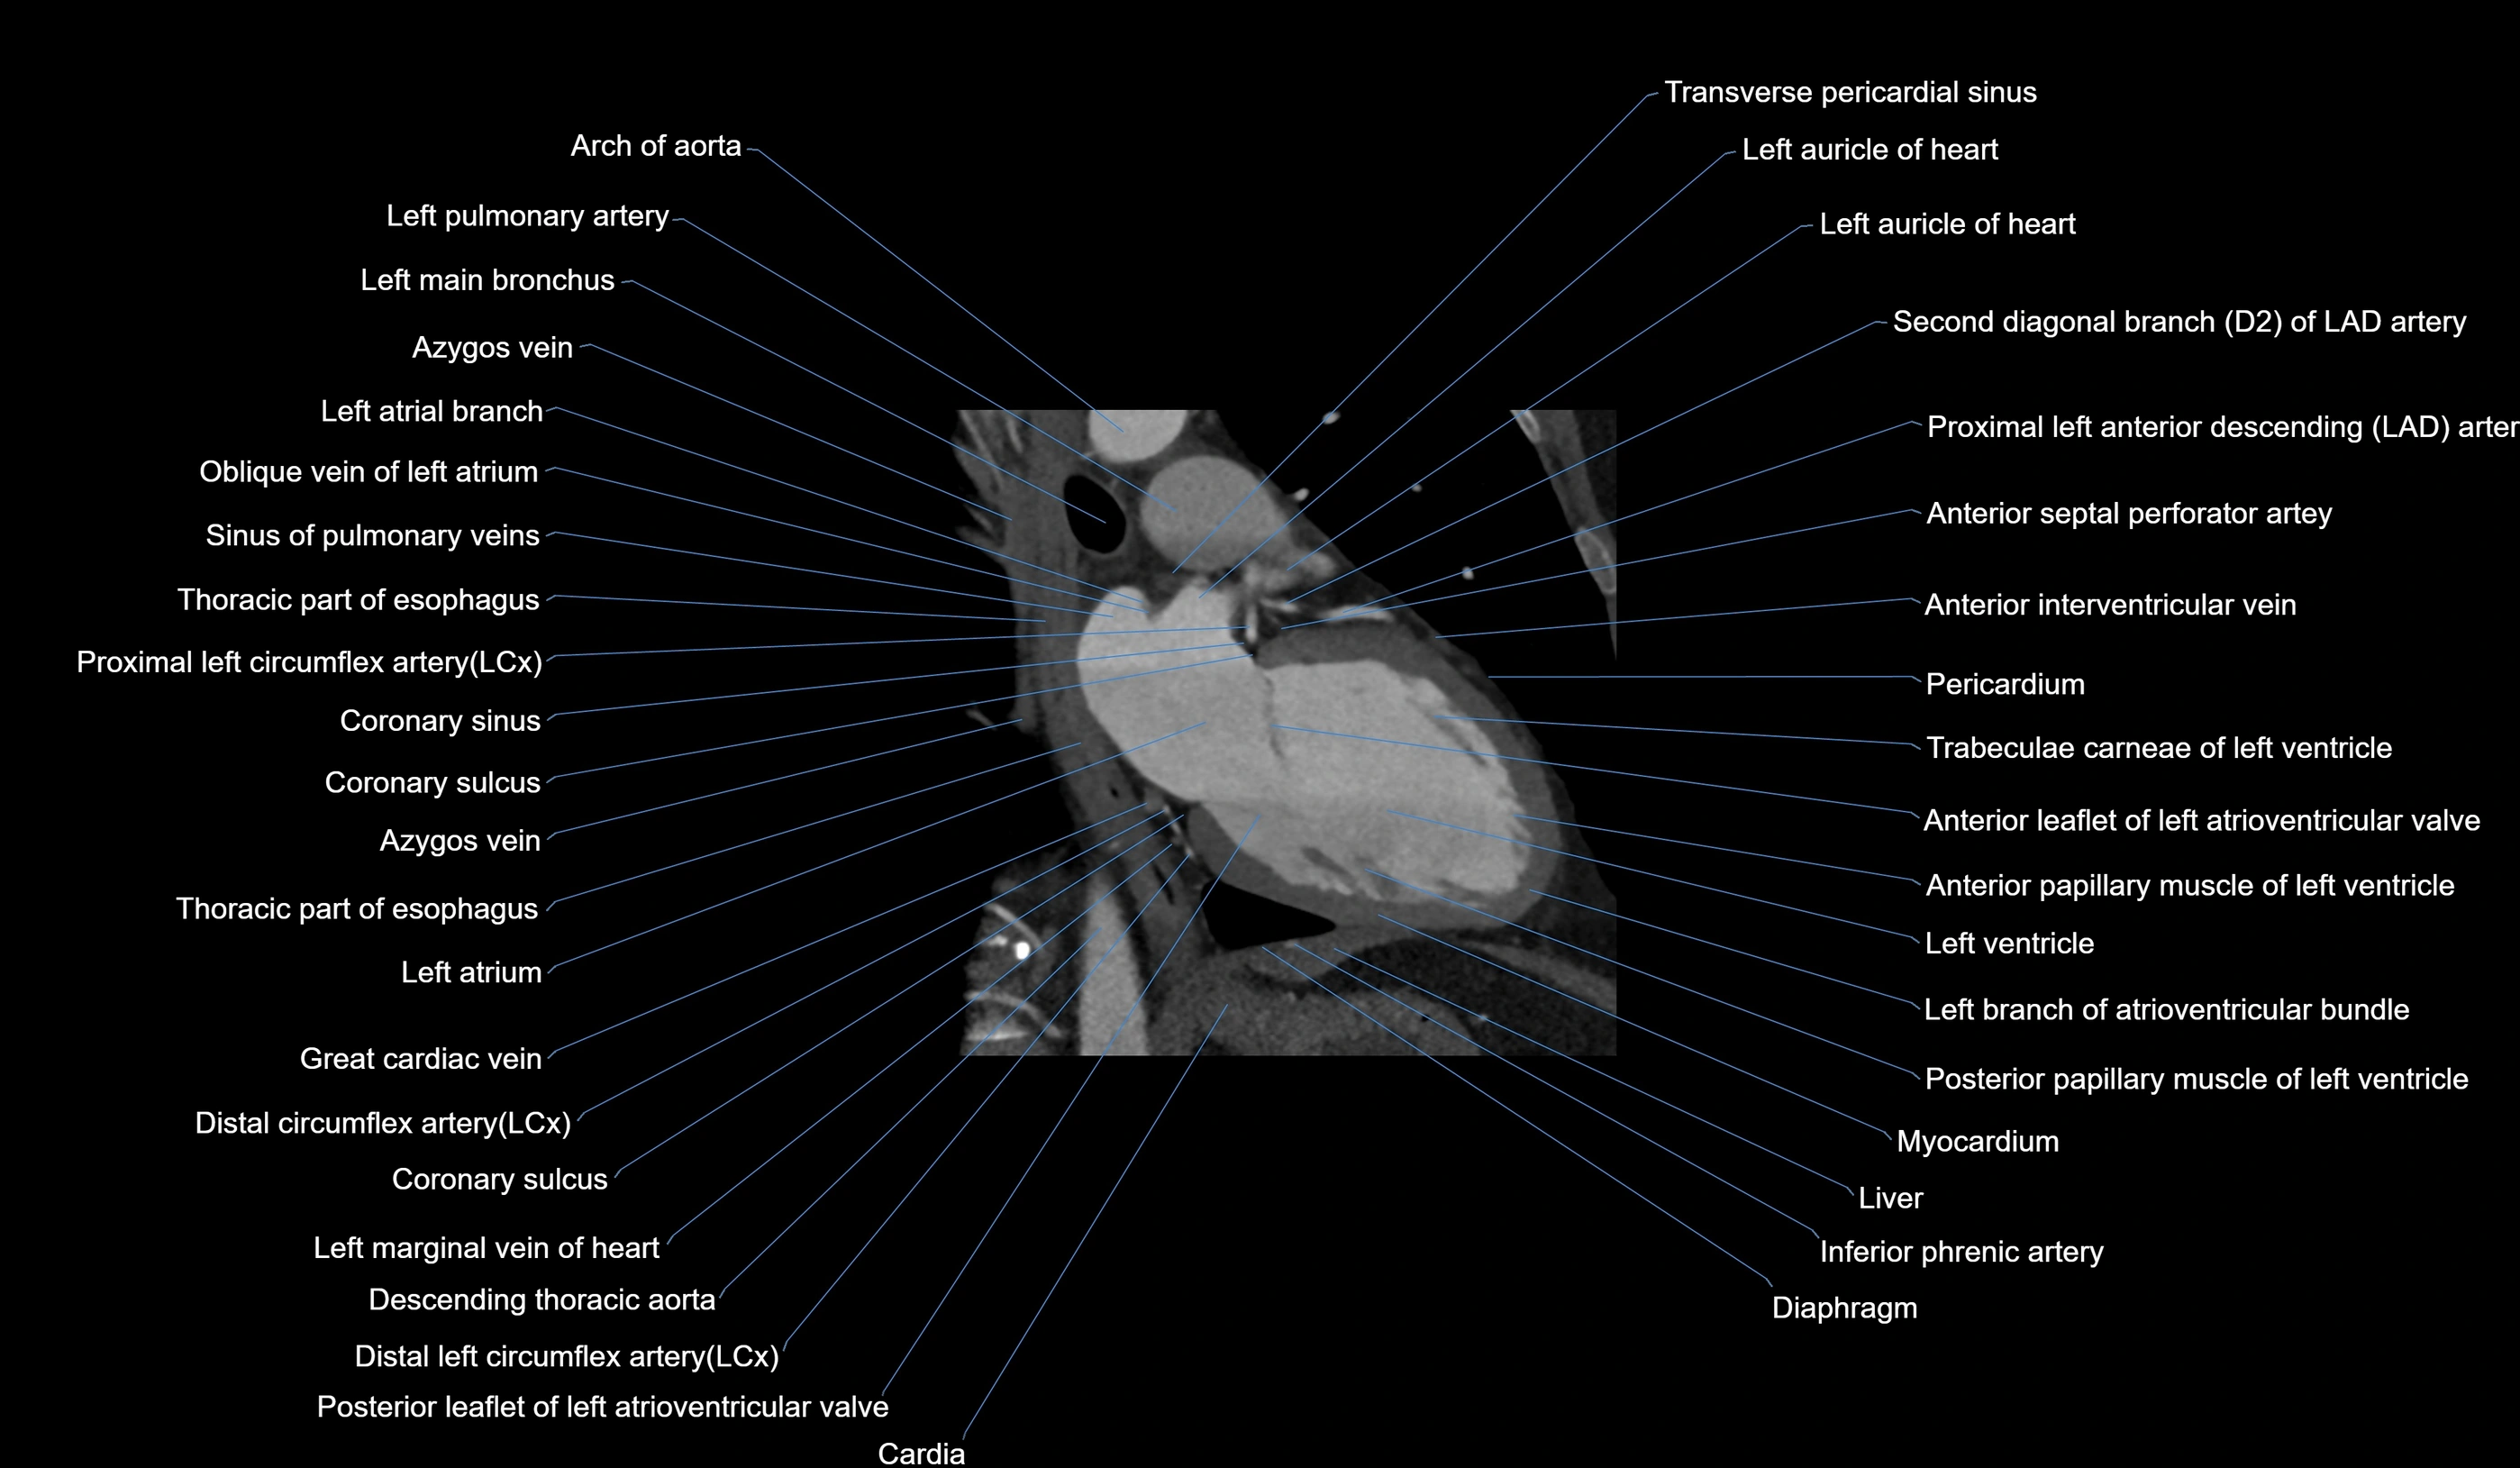

- Left atrium

- Left ventricle

- Left anterior descending artery (LAD)

- Circumflex artery (LCx)

- Left main coronary artery (LMCA)

- Great cardiac vein

- Left atrioventricular valve (mitral or bicuspid valve)

- Posterior leaflet of left atrioventricular valve

- Left branch of atrioventricular bundle

- Left pulmonary artery

- Left main bronchus

- Transverse pericardial sinus

- Oblique vein of left atrium

- Descending thoracic aorta